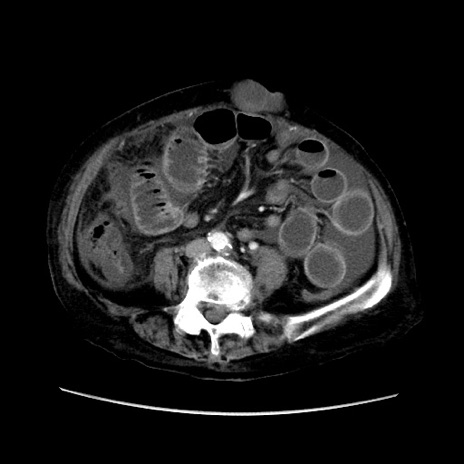

症例31(横断像)

【症例】80歳代 女性

【主訴】腹部膨満感

【現病歴】他院にて肝硬変にてフォロー中。1週間前から便秘、腹部膨満感、臍部腫瘤あり受診となる。

【既往歴】肝硬変

【身体所見】腹部膨隆あり、皮膚変化なし、疼痛なし。

【データ】WBC 4600、CRP 0.25